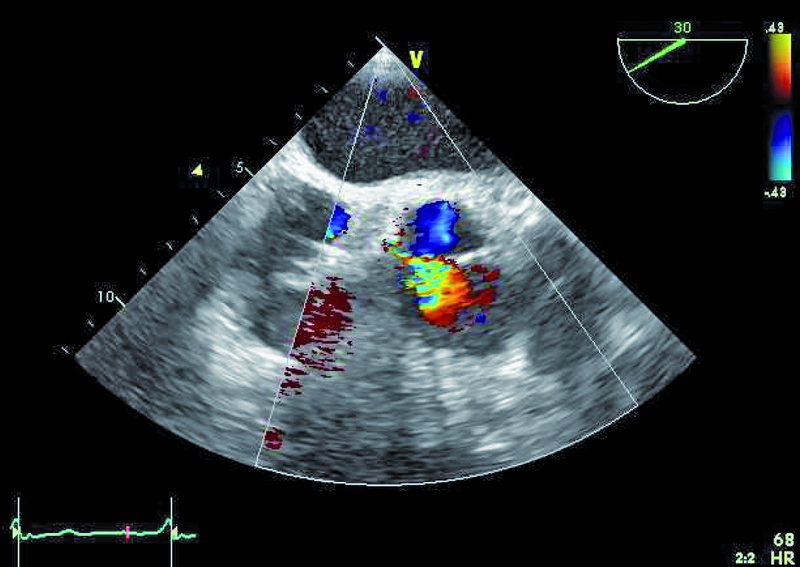

Mężczyzna, lat 25. Jakie patologie można rozpoznać na rycinach?

3. Drobne zmiany organiczne płatków zastawki aortalnej (ryc. 3).

4. Mała niedomykalność aortalna (ryc. 3, 4).